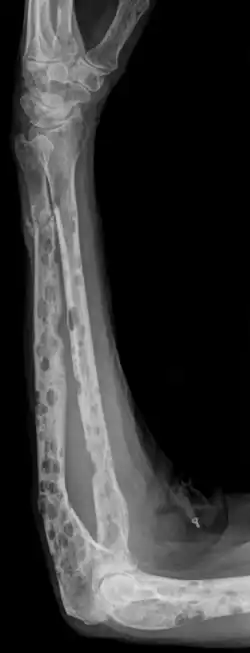

Морфология

Опухолевая ткань разрастается преимущественно в плоских костях (череп, рёбра, таз) и в позвоночнике, инициируя в них остеолизис[6] и остеопороз. На рентгенограмме очаги поражения имеют вид гладкостенных пробоин. Полости образуются в местах роста миеломных клеток за счёт активации ими остеокластов, осуществляющих лизис и резорбцию костной ткани («пазушное» рассасывание). Помимо костного мозга, опухолевые инфильтраты могут обнаруживаться и в других органах.

Множественная миелома может проявляться патологическими переломами, болями в костях, мягкотканными компонентами, анемическим синдромом, снижением гемоглобина, синдромом гипервязкости, тромбозами и кровотечениями. Вследствие разрушения костей в крови увеличивается количество кальция, который в виде конкрементов откладывается в выделительных органах (почки, лёгкие, слизистая желудка). Поражение почек (миеломная нефропатия) в основном обусловлено поступлением через почечный фильтр парапротеинов. Характерным для миеломной болезни является частота бактериальных инфекций вследствие уменьшения количества нормальных иммуноглобулинов и нарушения образования антител.